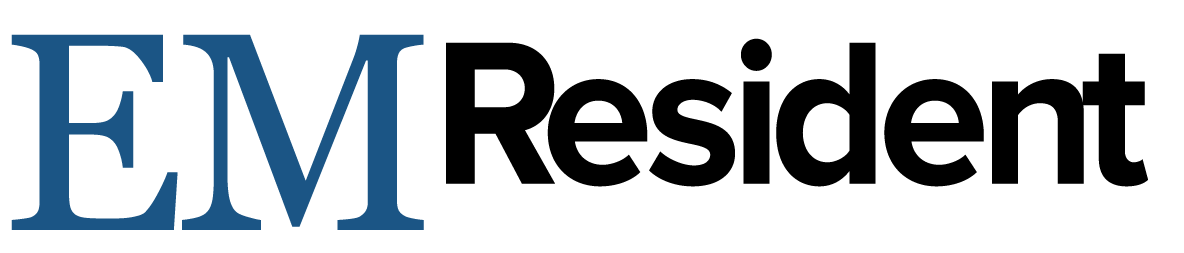

Ultrasound exam for cardiac tamponade must logically start with identification of a pericardial effusion. Emergency medicine physicians have shown that they can use point of care ultrasound with high sensitivity and specificity to find effusion.3 Acute effusions, such as in trauma, can be significant even when very small. If the pericardial space does not have time to stretch and accommodate the new fluid, pressure will rise quickly as it is inversely related to the volume the fluid occupies. The identification of any pericardial effusion in a hypotensive trauma patient should be considered evidence of tamponade until proven otherwise. Chronic effusions, however, can become very large before the development of tamponade physiology.4

Figure 1: Pericardial effusion